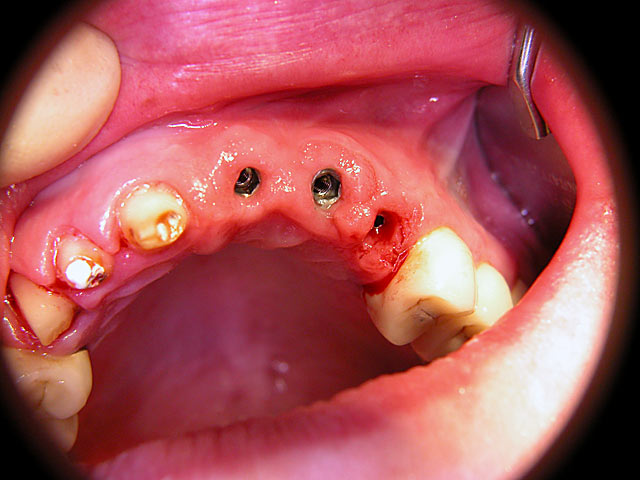

Die folgenden Patientenfälle sollen Ihnen einen Einblick in die Möglichkeiten der modernen Implantation geben.

Implantation mit fester Brücke: